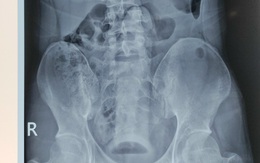

Cụ ông nhập viện với quả đạn pháo trong... trực tràng

Lực lượng tháo gỡ bom mìn được huy động, bệnh viện buộc phải sơ tán giữa đêm khi một cụ ông xuất hiện với một quả đạn pháo trong trực tràng. Một quả đạn pháo khá là... ố dề luôn đó bà con?!